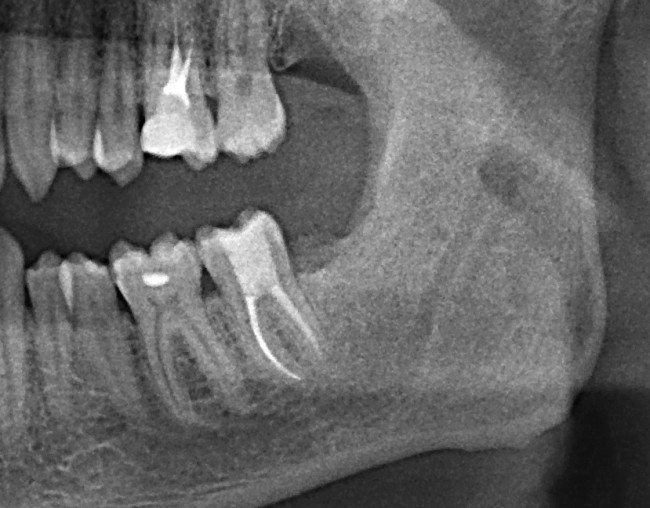

Вот наглядный пример такого того, к чему может привести несвоевременное удаление зуба мудрости. И не болит же! Мужчина обратился совсем с другой проблемой, обнаружили случайно, когда сделали панорамный снимок зубов.

Из-за неправильного положения 8ки на контактной поверхности зуба номер 7, образовалась достаточно глубокая кариозная полость, уходящая глубоко под десну.

Зуб мудрости успешно удален, а вот семерка на очереди… (8ка поделена на три фрагмента — коронковая часть и два корня)

Казалось бы, нормальный зуб. «Ну кариес, вон, пломба стоит одна, поставить еще одну, делов-то!». Все не так просто, так как кариозная полость уходит глубоко под десну, подобные зубы лечению не подлежат. Почему? Потому что при постановке пломбы, обработанная полость должна быть сухой. Добиться этого при таком поражении невозможно. Как минимум из-за того, что в десне содержится «десневая жидкость», которая постоянно будет подтекать в эту область.